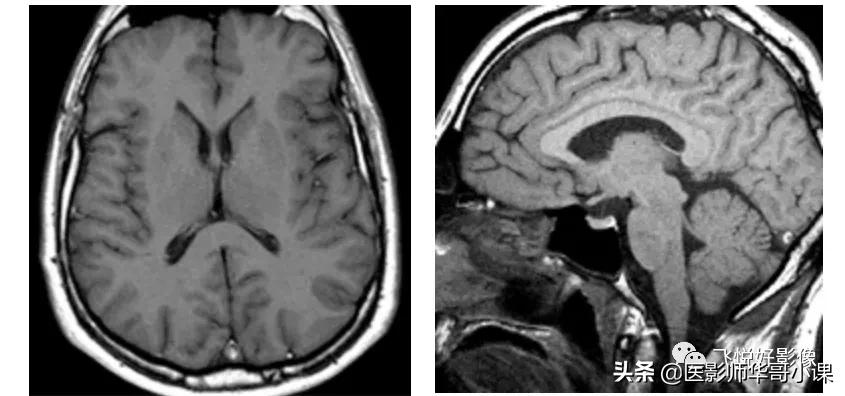

图2,SE T1加权图像。左图为横断面脑实质T1加权图像,TR=582ms,TE=12ms。右图为矢状面脑实质T1加权图像,TR=480ms,TE=12ms。T1加权图像主要用于显示脑实质解剖结构,脑白质相对于脑灰质显示为稍高信号;脑脊液在T1加权图像中为低信号,皮下脂肪组织、骨髓脂肪组织显示为高信号,而骨结构、空气等在磁共振中不产生信号。(图像源自飞利浦磁共振系统)